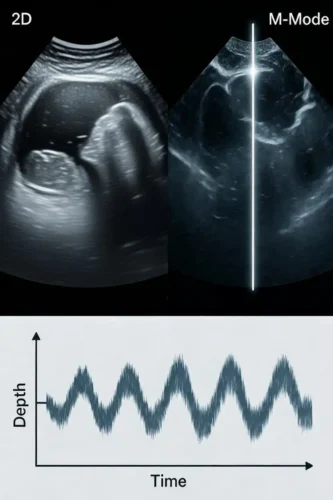

اکوی M‑Mode یا Motion Mode در اصل قدیمیترین و در عین حال یکی از دقیقترین مدهای اکوکاردیوگرافی است که برای ثبت حرکت ساختارهای قلب در طول زمان بهکار میرود. در این مد، دستگاه بهجای تولید یک تصویر دوبعدی از کل مقطع قلب، فقط یک «خط» از تصویر را انتخاب میکند و تغییرات عمق اکوهای بازتابشده از آن خط را در طول زمان ثبت میکند. نتیجه، یک نمودار تکبعدی است که در آن محور افقی زمان و محور عمودی عمق است؛ یعنی میتوان دید که یک ساختار (مثلاً دیواره بطن یا لِفلت دریچه) در هر لحظه از زمان در چه موقعیتی قرار دارد و چگونه حرکت میکند. همین سادگی ظاهری، دقت زمانی بسیار بالایی ایجاد میکند و M‑Mode را به یک ابزار فوقالعاده برای اندازهگیریهای دقیق تبدیل میکند.

حالا دستگاه این اطلاعات را روی یک نمودار خاص نمایش میدهد:

- محور عمودی (Y) : عمق از پروب (فاصله ساختار از سطح پوست/پروب)

- محور افقی (X) : زمان (لحظههای متوالی اسکن)

هر بار که خط اسکن تکرار میشود، پروفایل عمقی اکوها (یعنی اینکه در چه عمقی چه ساختاری وجود دارد) روی یک «ستون عمودی» جدید در سمت راست نمودار رسم میشود. با گذشت زمان، این ستونها پشتسر هم قرار میگیرند و یک تصویر نوارمانند تشکیل میدهند. نتیجه این است که حرکت یک ساختار در طول زمان، بهصورت یک منحنی یا الگوی موجی روی صفحه ظاهر میشود.

مثلاً اگر خط M‑Mode از روی دیواره قدامی و خلفی بطن چپ عبور کند، هر بار که قلب منقبض و منبسط میشود، فاصله این دیوارهها از پروب تغییر میکند. این تغییر فاصله، روی نمودار بهصورت نزدیک و دور شدن خطوط روشن (نمایانگر دیوارهها) از هم دیده میشود. در سیستول، دیوارهها به هم نزدیک میشوند (فاصله کمتر، خطوط به هم نزدیکتر)، و در دیاستول از هم دور میشوند (فاصله بیشتر، خطوط از هم دورتر). همین الگوی تکرارشونده است که امکان اندازهگیری LVIDd، LVIDs و ضخامت دیوارهها را میدهد.

پس اگر بخواهیم در یک جمله جمعبندی کنیم:

در M‑Mode، دستگاه یک خط ثابت از قلب را بارها در طول زمان اسکن میکند، عمق اکوهای بازتابی را روی محور عمودی و زمان را روی محور افقی میگذارد، و با کنار هم چیدن این پروفایلها، یک تصویر نوارمانند میسازد که حرکت ساختارهای قلب را در طول زمان، بهصورت تکبعدی اما با دقت زمانی بسیار بالا نشان میدهد. در اکوی M‑Mode عملاً داری یک «نمودار» میبینی، نه فقط یک تصویر ساده؛ و فهمیدن محور زمان و محور عمق یعنی دقیقاً بفهمی این نمودار چه میگوید.

⬇️محور عمق (Depth) – محور عمودی تصویر

محور عمودی در M‑Mode نشاندهنده فاصله ساختارهای قلب از پروب است؛ یعنی همان «عمق». هرچه یک ساختار به پروب نزدیکتر باشد، در بخش بالاتر تصویر دیده میشود؛ هرچه دورتر باشد، پایینتر ظاهر میشود.

➡️محور زمان (Time) – محور افقی تصویر

محور افقی در M‑Mode نشاندهنده گذشت زمان است؛ یعنی هر نقطهای که از چپ به راست میبینی، یک لحظه جدید از حرکت قلب است. در هر لحظه، دستگاه یک پروفایل عمقی از اکوها در امتداد خط M‑Mode ثبت میکند (یعنی اینکه در هر عمق چه ساختاری هست). این پروفایل بهصورت یک «ستون عمودی» روی تصویر رسم میشود. لحظه بعد، ستون بعدی کنار آن قرار میگیرد، و همینطور تا سمت راست تصویر ادامه پیدا میکند. نتیجه این است که: